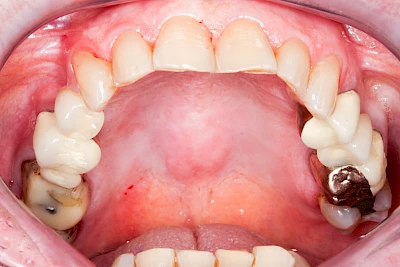

Knochenschwund (Atrophie)

Gehen die Zähne verloren, baut häufig auch der Kieferknochen ab (Knochenschwund). Die Geschwindigkeit und das Ausmaß des Knochenschwundes ist von vielen Faktoren abhängig. Neben der genetischen Veranlagung spielen auch Überbelastungen in Folge, z. B. bei ständigem Knirschen oder Pressen, eine Rolle. Auch wenn Zahnprothesen Tag und Nacht getragen werden, kann die ständige Belastung der Schleimhäute und des Knochens den Knochenschwund beschleunigen.